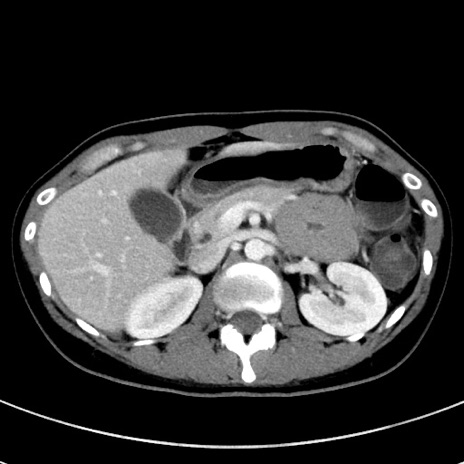

症例17(横断像)

【症例】20歳代女性

【主訴】嘔吐、下腹部痛

【現病歴】昨日夕食後に嘔吐し下腹部痛が出現。本日になっても嘔吐持続し改善しないため来院。

【身体所見】意識清明、BT 37.2℃、BP 108/67mmHg、腹部:平坦、やや硬、下腹部正中から右にかけて圧痛あり、反跳痛軽度あり、tapping pain(+)。

【データ】WBC 13600、CRP 14.94